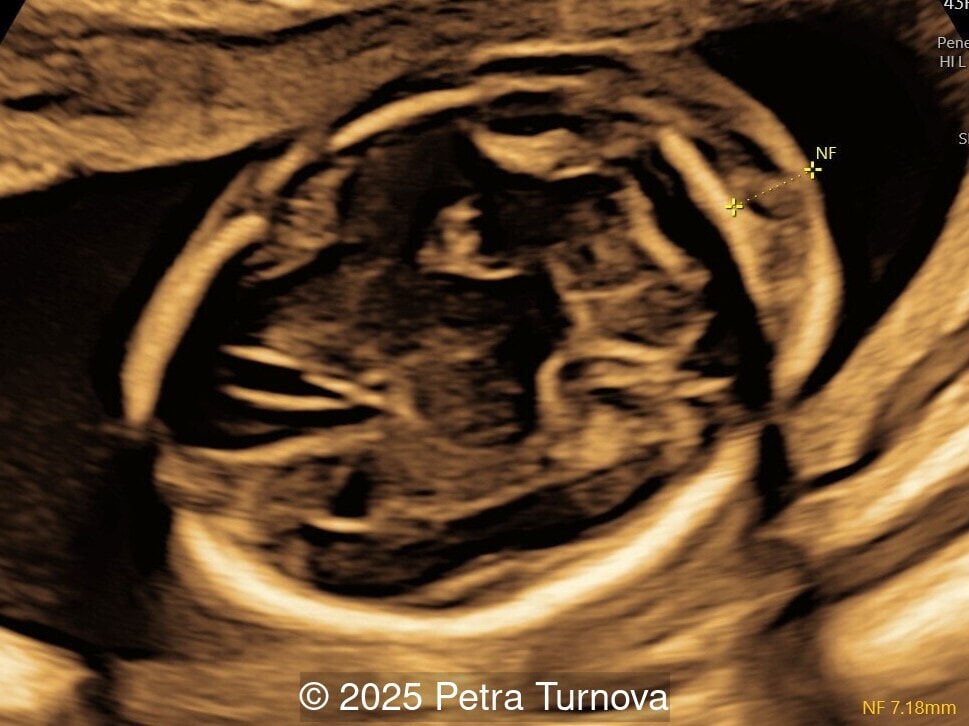

Ultrasound examination revealed abnormal subcutaneous tissue and abnormal nuchal fold highly suggestive of trisomy 21. In addition, a marked hepatomegaly was noted, with the liver appearing diffusely hyperechogenic. No ascites or signs of hydrops were present.

Given the constellation of findings, Trisomy 21 with associated hematologic involvement, most likely transient myeloproliferative disorder, was suspected. The patient underwent amniocentesis, which confirmed Trisomy 21. After multidisciplinary counseling, the patient opted for termination of pregnancy, which was performed at 20 weeks gestation. A fetal autopsy was performed. External examination confirmed facial dysmorphism characteristic of Down syndrome, including a flat nasal bridge and epicanthic folds. Internal examination revealed marked hepatosplenomegaly with the liver weighing approximately 2.5 times the expected weight for gestational age and demonstrated diffuse pale nodularity. Histopathologic examination showed massive extramedullary hematopoiesis with numerous immature megakaryoblasts, large atypical nuclei, and frequent mitotic figures within the hepatic sinusoids and portal areas. Similar infiltrates were present in the splenic red pulp and occasionally in the bone marrow, confirming the diagnosis of transient myeloproliferative disorder in association with Trisomy 21. This case underscores the importance of recognizing fetal hepatomegaly with dysmorphic features of Trisomy 21 as a potential marker of transient myeloproliferative disorder, prompting targeted cytogenetic testing and appropriate counseling.

From the prenatal diagnostic viewpoint, the combination of trisomy 21 and hepatosplenomegaly on ultrasound should prompt suspicion of transient myeloproliferative disorder [1,4]. The disease can manifest as fetal hepatosplenomegaly, hydrops fetalis, polyhydramnios, or placentomegaly [4,5]. The enlarged fetal liver, often hyperechogenic, reflects massive extramedullary hematopoiesis and infiltration by megakaryoblasts. Splenic enlargement and occasional ascites or pericardial effusion may accompany the presentation. Doppler studies may show increased middle cerebral artery peak systolic velocity due to fetal anemia [5,6]. Cytologically, peripheral blood and fetal liver aspirates reveal increased circulating blasts, often with megakaryoblastic morphology (irregular nuclei, cytoplasmic blebs, and platelet peroxidase positivity). Bone marrow may be normocellular or show hypocellularity with increased immature megakaryocytes [2].